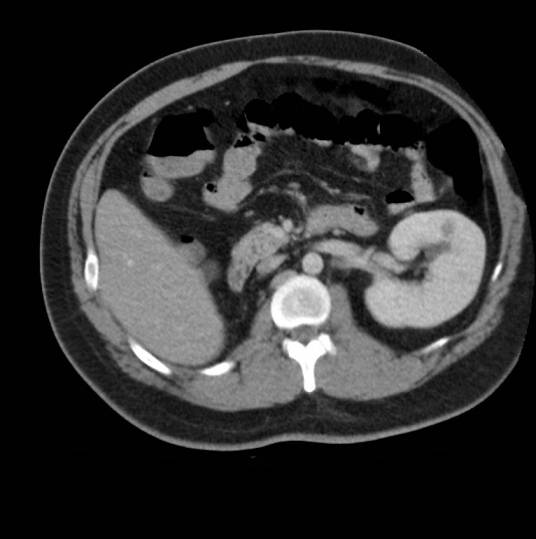

诊断孤立肾须通过详细的体格检查、静脉肾盂造影、CT等作出正确诊断,对于孤立肾并发结石和梗阻或感染,手术时要注意保存具有肾功能的组织。应加强监测,并发症处理应及时有效,防止肾功能不全发生。

在胚胎时期,肾的发育过程包括原肾、中肾及后肾3个阶段,其中任何一个阶段发生紊乱,都可能引起肾先天性异常。当一侧生肾组织或输尿管芽等生长紊乱,未能发育,即形成孤立肾。其在临床上多无特殊表现,影象学检查是明确诊断的主要手段。传统的x线检查带局限性,现已少用或不用,腹膜各充气造影亦被淘汰,腹主动脉造影虽可能获得明确诊断,但其为有创伤性检查;B超检查简便经济,亦较准确及时,但毕竟有一定的误诊率CT检查扫描是诊断先天性孤立肾最可靠的方法,它同时还能观察孤立肾本身及其周围脏器的病变。但CT扫描费用较高,可以认为诊断孤立肾可首选B超检查,在无法确定诊断的悄况下再辅以CT扫描比较适宜 。

MSCT对孤立肾的诊断:结合平扫、增强扫描薄层图像综合分析可以明显提高本病诊断的敏感性及特异性。增强扫描时将增强的肾上腺分支或连于肾静脉的性腺静脉误认为是肾发育不良,而肾发育不全、肾发育不良及异位肾也易于误诊为本病,在诊断中应予以注意。孤立肾并发结石的危害要明显高于普通人群,更需要积极、早期治疗以防发生肾衰竭 。